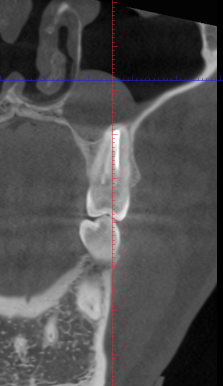

Снимок1.PNG

Смотри какая хуйня. Удалял зуб лет 5 назад. Сегодня делал КТ для ортодонта и вот такую хуйню нашел. Че делать теперь? Удалял в государственной поликлинике, чеков конечно не осталось. Как мне теперь им предъявить?

Мне это в стамотологии смогут это вынуть или в ЛОР больницу придется идти на операцию?